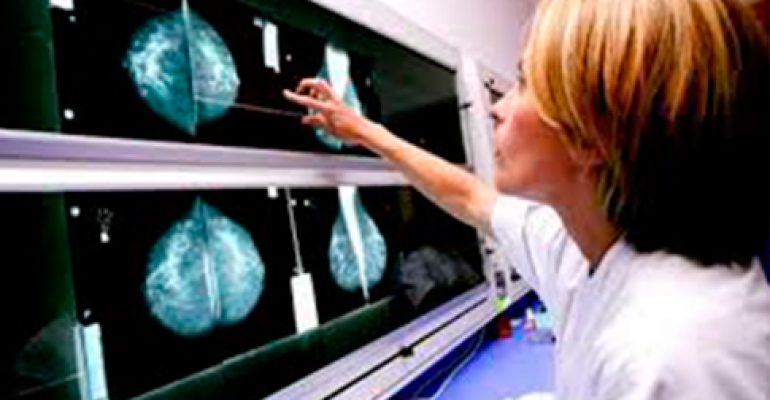

CON LA DIAGNOSI PRECOCE SI GUARISCE DAL TUMORE AL SENO